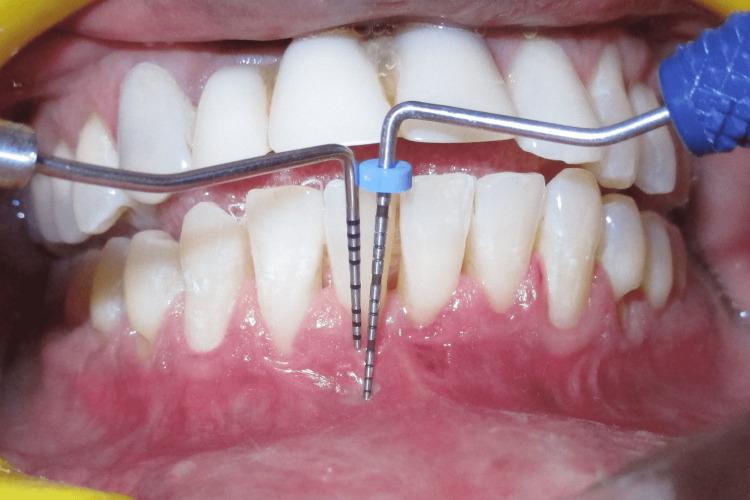

This case report describes Clark's technique of vestibuloplasty to treat shallow vestibule and, in addition, the use of free gingival autograft to augment attached gingiva to treat Miller's recession. Vestibuloplasty is performed to deepen a shallow vestibule. Different vestibuloplasty techniques are used to deepen the shallow vestibule by modifying the soft tissue attachment. A 29-year-old male presented to the Department of Periodontics and Oral Implantology, Regional Dental College, Guwahati, India with the chief complaint of bleeding from the lower anterior along with the gingival recession. Maintenance of regular oral hygiene was an added hindrance. The combined technique of vestibuloplasty and use of free gingival graft was performed to achieve dual benefits of increasing the vestibular depth and attainment of a thick gingival phenotype.

本病例报告描述了克拉克前庭成形术治疗浅前庭的技术,此外,还介绍了使用游离龈自体移植术增加附着龈以治疗米勒氏牙龈退缩的方法。前庭成形术用于加深浅前庭。通过改变软组织附着来加深浅前庭,采用了不同的前庭成形术技术。一名29岁男性因下前牙出血伴牙龈退缩,前往印度古瓦哈蒂地区牙科学院牙周病与口腔种植科就诊。保持规律的口腔卫生是一个额外的障碍。采用前庭成形术和游离龈移植术相结合的技术,以实现增加前庭深度和获得厚龈表型的双重益处。